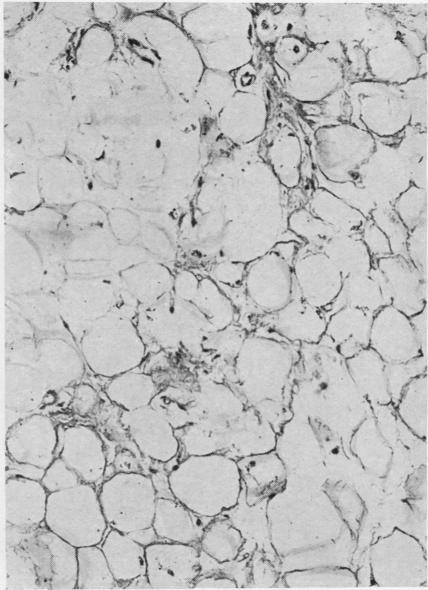

Primary amyloidosis: a review.

J Clin Pathol. 1956 Aug;9(3):187-211. doi: 10.1136/jcp.9.3.187.